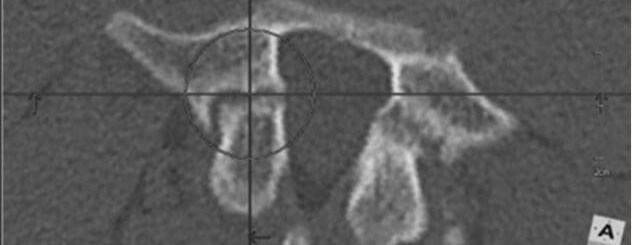

Very often it is necessary to carry out additional diagnosis. Ideal in this situation will be a CT scan, which perfectly shows the bone and its structure. Very often, a Spondylolysis is such a tiny fissure, which is less than a millimeter within the bone. The problem may be that 13-, 14- or 15-year-old children should not have a CT scan, except in special cases like cancer. Some MRI labs, including those at Rehasport Clinic, have a special program for processing MRI images. This is called an isovolumetric MRI, and you can see the vertebrae from it, because it gives a spatial image.